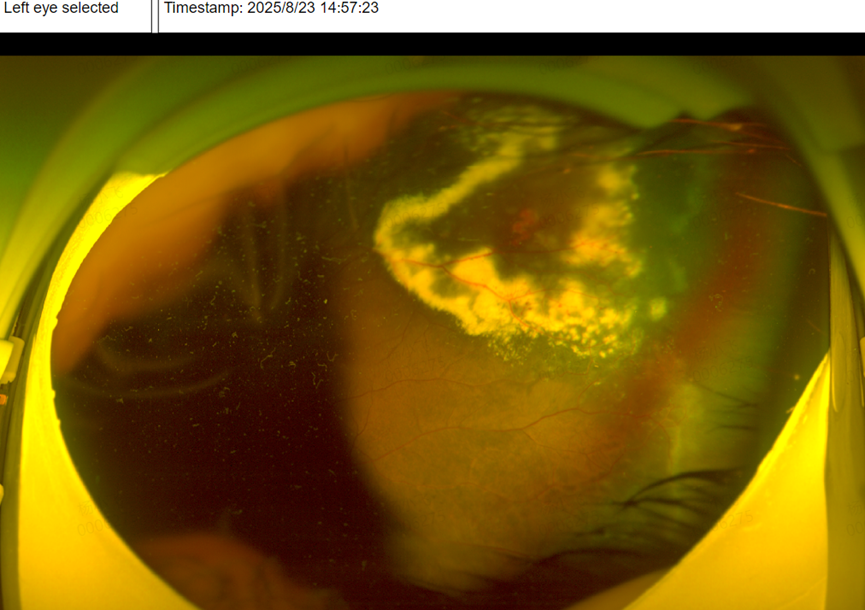

可检查结果让所有人揪心——孩子左眼患上了「外层渗出性视网膜病变(Coats 病)」,这是一种多见于儿童的眼底疾病,早期症状隐匿,很容易被忽视。幸运的是,由于筛查及时,孩子已被迅速转诊至辽宁爱尔眼科医院眼底专家团队,后续将接受针对性治疗,为保住视力争取到了宝贵时间。

「如果当时只查了近视度数,没做眼底检查,这个孩子的病情可能会被继续耽误,等到出现明显症状时,视功能损伤可能已经不可逆了。」爱尔眼科辽宁省区副总院长杨积文教授对此深有感触,也希望通过这个案例,让更多家长重视儿童眼底筛查的重要性。

而确诊 Coats 病,需要依靠专业的眼科检查,比如「荧光素眼底血管造影」(能清晰看到眼底血管的异常扩张)、「眼部 B 超」,必要时还会做 CT 检查,用来和其他类似疾病(如视网膜母细胞瘤)区分开,避免误诊。